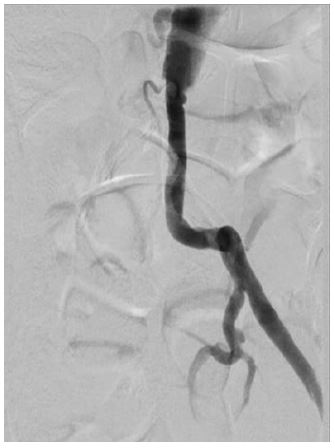

A female patient, 71 years old, active smoker, with arterial hypertension and diabetes, was admitted with right inferior limb rest pain. The patient was submitted to Angioct-Scan which demonstrated common iliac arteries bilateral occlusion. The patient was submitted to endovascular surgery with an iliac kissing stent and implant of Wrapsody 8×50 mm at the right common iliac artery and Wrapsody 7×75 mm at the left common iliac artery, followed by post-dilatation with a catheter balloon. (Figure 3). The patient was discharged from the hospital first day post-operative and 1-month follow-up showed endoprosthesis patency with complete resolution of the previous symptoms.

Figure 3: Iliac kissing stent and implant of Wrapsody 8×50 mm at the right common iliac artery and Wrapsody 7×75 mm.